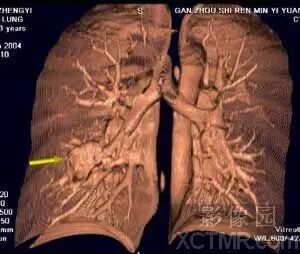

IVR图象显示支气管与肺部肿瘤之间的关系,此病例虽然没有进行增强,

但是通过图象后处理仍然清晰地 显示出肺内支气管及肿瘤组织,并且可以看到肿瘤支气管关系密切。